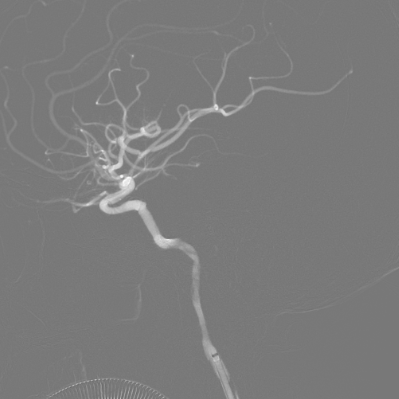

右侧颈内动脉造影动脉末期可见左侧大脑前动脉经软膜支向左侧大脑中动脉供血区域代偿,后循环未向左侧大脑中动脉代偿。

左侧颈总动脉造影可见颈内动脉闭塞,动脉末期可见颈外动脉经眼动脉向颈内动脉代偿,颈内动脉末端以远不显影。